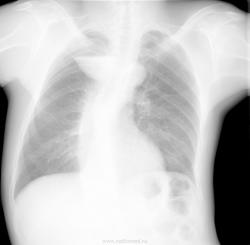

Как ни старайся, а верхушка не воздушна... Всё-таки на мой взгляд, это менее похоже на уровень жидкости, не хватает воздуха над ним. Барий нужен, несомненно. Но пока я за осумкованный плеврит.

Думаю дифференциальный ряд должен включать - частично дренированый абсцесс верхушки, осумкованый плеврит; дивертикул пищевода.

Необходимо - правая боковая проекция; возможно рентгеноскопия с контрастированием пищевода.

Первая мысль была про дивертикул пищевода, но смутил тяж к плевре. Нужно боковую проекцию и барий

В этом месте часто проходит добавочная междолевая борозда доли непарной вены, вероятно осумкованный плеврит именно там.

+1 за плеврит в доле v. azygos